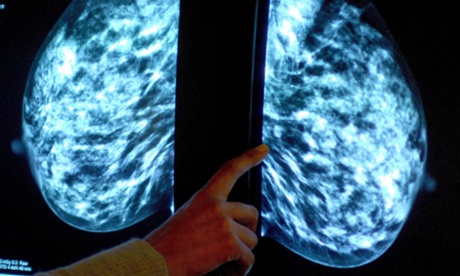

A mammogram showing a breast tumour. Around half of all women diagnosed with breast cancer each year could potentially benefit from the latest findings.

A mammogram showing a breast tumour. Around half of all women diagnosed with breast cancer each year could potentially benefit from the latest findings. Photograph: Rui Vieira/PA